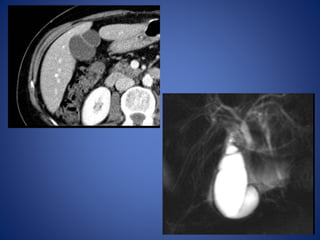

• 45.

Choledochal Cysts Choledochal cystsare congenital cystic dilatations of any portion of extra hepatic bile ducts, most commonly the main portion of CBD. It is postulated that this condition begins with an anomalous junction of the common bile duct and pancreatic duct proximal to the duodenal papilla. Higher pressure in pancreatic duct combined + an absent ductal sphincter allows free reflux of enzymes into biliary tree, weakening wall of the common bile duct. Normal Abnormal

Diagnosis of acholedochal cyst is made on the basis of disproportional dilatation of the extrahepatic bile ducts after excluding the possibility of a tumor, stone, or inflammation as the cause of the dilatation. The estimated incidence of choledochal cysts in Western countries varies between 1 in 100,000 and 1 in 150,000 individuals. The rate of incidence is higher in Asia and occurs more frequently in women (M: F- 4:1).60% of patients present before age 10, although choledochal cysts can present from birth to old age. This anomaly is associated with increased incidence of GB anomalies, biliary anomalies ( stenosis /atresia), and congenital hepatic fibrosis. Complications of choledochal cysts in adults include rupture with bile peritonitis, secondary infection (cholangitis), biliary cirrhosis and portal hypertension, calculus formation, portal vein thrombosis, liver abscess, hemorrhage, and malignant transformation into cholangiocarcinoma.

• 50.

Newborns and infantspresent with obstructive jaundice. Older children and adults may have the classic triad of right upper quadrant pain, intermittent jaundice, and a palpable right upper quadrant mass. In adult patients, a choledochal cyst is often first diagnosed on cross- sectional imaging. CT and ultrasound demonstrate a fluid-filled structure beneath the porta hepatis separate from the gallbladder that communicates with the hepatic ducts. An abrupt change in the caliber of the ducts occurs at the site of the cysts. Intrahepatic ductal dilatation may be present as well.